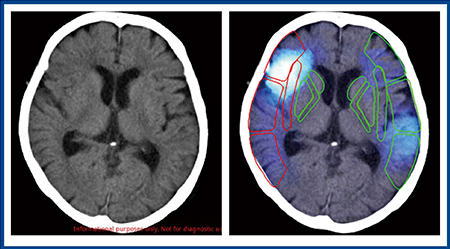

Ischemia analysisでは,脳梗塞の低吸収域を抽出し,early CT signの確率が高い領域を強調表示する。さらに,Ischemia analysisでは早期虚血性変化を定量化したスコア法である“CT-ASPECTS”の算出を補助することができる。CT-ASPECTSは,前方循環領域の早期虚血性変化を10のエリアに分け,その虚血の程度,重症度をスコアリングしていく。虚血なしが10点で,虚血があるエリアごとに減点していき,中大脳動脈(MCA)全領域に虚血があれば0点となる。一般的には7点以下で“広範な虚血性変化”となり,tPA投与によって出血のリスクが上昇すると判断される。

図3は,計算ができない,左右がわからないという主訴で来院した症例である。専門医ならば,左のMCA領域に梗塞を疑うが,非専門医では読み取るのが難しいと思われる。Ischemia analysisでは,虚血をピックアップして,CT-ASPECTSにより虚血があるエリア(減点)を赤枠で示し点数を自動計算する。また,図4では,右の大脳半球に広範な低吸収域が認められるが,Ischemia analysisの虚血サインは左のM5,M6領域を指している。右の低吸収域は古い梗塞巣と判断され,陳旧性病巣は除外できるのもポイントである。

図3 Ischemia analysisのCT-ASPECTS自動計算1